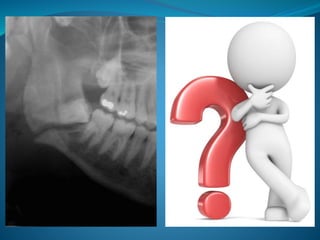

Mandibular angle fractures account for 23% to 42% of all

facial fractures (1). The most common causes of

Mandibular angle fracturesaccount for 23% to 42% of all facial fractures (1). The most common causes of mandibular angle fractures are motor vehicle accident and assaults or violence. There are two main proposed reasons why the angle of the mandible is commonly associated with fractures. The first reason is the presence of a thinner cross-sectional area relative to the neighboring segments of the mandible (2). Second is the presence of third molars, particularly those that are impacted, which weakens the region (3)

An importance ofclassification of mandibular angle fractures relates to direction of the fracture line and effect of muscle action on the fracture fragments. Thus, fractures have been classified as: a. Vertically favorable or unfavorable b. Horizontally favorable or unfavorable Muscles attached to the ramus masseter, temporalis and medial pterygoid displace the proximal segment upward and medially when the fractures are unfavorable; conversely these same muscles tend to impact the bone, minimizing displacement in horizontal and vertical favorable fractures (4)